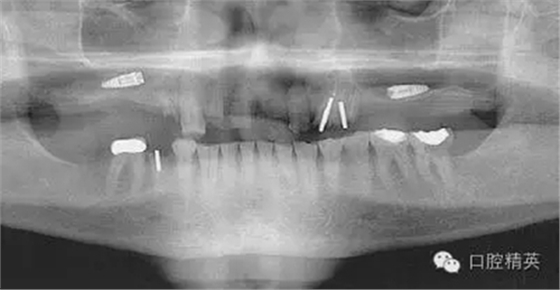

圖2a:術(shù)后曲面斷層片顯示兩顆種植體分別異位于左右側(cè)上頜竇中

圖2b:術(shù)后斷層片顯示一顆種植體異位于右側(cè)上頜竇中,ICATCBCT顯示了種植體在上頜竇頰舌方向上的位置對(duì)于同一位點(diǎn),不同角度的圖像可以一一呈現(xiàn),將猜測(cè)拒口腔種植之門(mén)外。另外,CBCT對(duì)放射線的利用率很高,大大降低了放射劑量,它的放射劑量遠(yuǎn)遠(yuǎn)小于拍攝全口根尖片(無(wú)論是數(shù)字牙片還是膠片牙片)的放射劑量。從牙醫(yī)的角度,CBCT的應(yīng)用同樣增加了他們的利潤(rùn)。